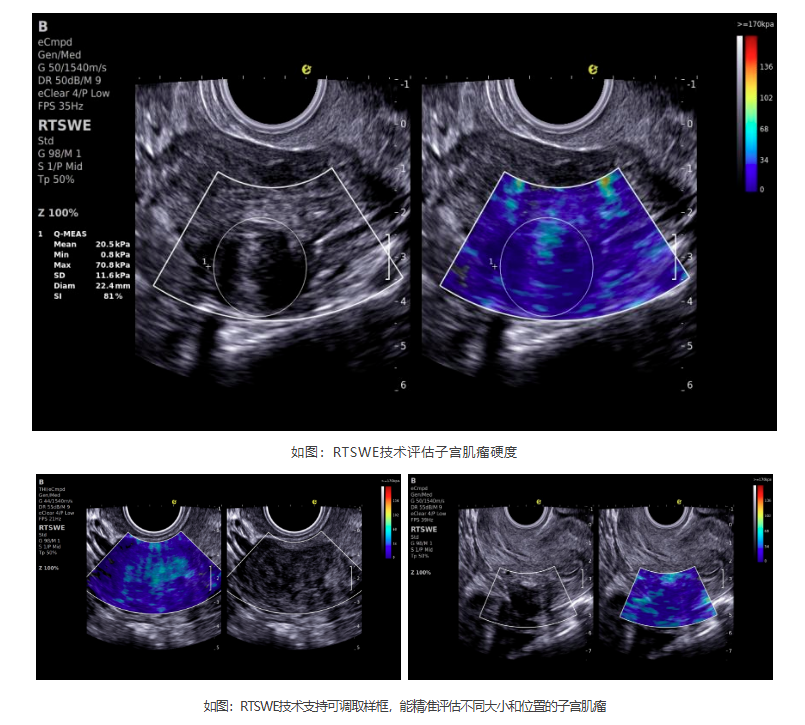

如今,银河官网医疗ePascal东风系列搭载的RTSWE?实时E成像技术为肌瘤良恶性的鉴别带来了突破!该技术基于OmniSound? 平面波超快速平台,以25000帧/秒的采集帧频,实现最小0.4mm病灶的精准硬度测量。它犹如为超声检查赋予"智能触诊"能力,通过定量分析组织硬度,辅助判断肌瘤性质:

良性肌瘤:质地均匀,硬度较高(类似橡皮)

恶性肉瘤:硬度不均,整体更坚硬(类似石头)

变性肌瘤:如红色变性时,硬度会相应降低

RTSWE?技术优势

? 安全无创——零辐射、无痛苦,检查更舒适

? 减少过度检查——降低不必要活检

? 生育友好——专为备孕女性定制肌瘤评估方案

? 动态监测风险——敏感捕捉绝经后肌瘤的异常

? 指导精准治疗——为手术决策提供客观依据

cd2301cd65513af0501835669682402.png

潜伏在子宫里的"小石头",看似无害,却需要及时关注。银河官网医疗RTSWE?实时E成像技术以毫米级精度实现子宫肌瘤可视化诊断,突破性探测病灶质地特性,为临床决策提供新维度。该技术助力女性通过精准超声检测,获得更安心的健康保障。